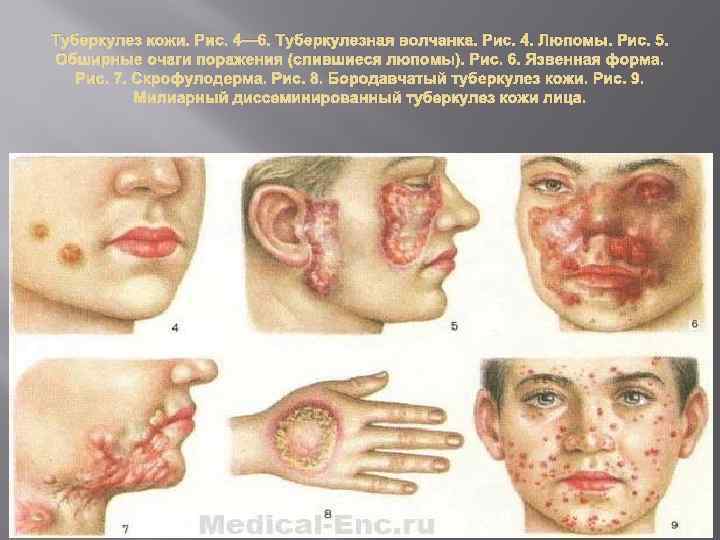

Туберкулезная волчанка, или волчаночный туберкулез кожи, развивается при заносе микобактерии туберкулеза в кожу гематогенным и лимфогенным путем. На коже лица (нос, губы, щеки, ушные раковины и др. ), на слизистой оболочке носа и рта, реже на коже туловища и конечностях появляются мягкие красновато-оранжевые бугорки диаметром от 0, 2 до 0, 8 см. Сливаясь, они образуют более крупные очаги поражения Колликвативный туберкулез кожи, или скрофулодерма, развивается вследствие попадания в кожу микобактерий туберкулеза преимущественно лимфогенным путем и по соприкосновению (из лимфатических узлов, суставов). Характеризуется появлением в дерме (собственно коже) и подкожной основе шаровидного узла диаметром 0, 5– 3 см. Чаще узел располагается в области крупных лимфатических узлов (поднижнечелюстных, шейных, подмышечных, паховых) и по краю грудины. Вначале узел небольшой, подвижный. Постепенно он увеличивается и спаивается с окружающими тканями. Кожа над ним истончается, приобретает синюшно-красный цвет. Затем узел некротизируется и прорывается в нескольких местах наружу с выделением жидкого гноя и крошковатых масс. После заживления остаются характерные неровные рубцы с «сосочками» и «мостиками» , позволяющие безошибочно ретроспективно установить перенесенный колликвативный туберкулез кожи.

Туберкулезная волчанка, или волчаночный туберкулез кожи, развивается при заносе микобактерии туберкулеза в кожу гематогенным и лимфогенным путем. На коже лица (нос, губы, щеки, ушные раковины и др. ), на слизистой оболочке носа и рта, реже на коже туловища и конечностях появляются мягкие красновато-оранжевые бугорки диаметром от 0, 2 до 0, 8 см. Сливаясь, они образуют более крупные очаги поражения Колликвативный туберкулез кожи, или скрофулодерма, развивается вследствие попадания в кожу микобактерий туберкулеза преимущественно лимфогенным путем и по соприкосновению (из лимфатических узлов, суставов). Характеризуется появлением в дерме (собственно коже) и подкожной основе шаровидного узла диаметром 0, 5– 3 см. Чаще узел располагается в области крупных лимфатических узлов (поднижнечелюстных, шейных, подмышечных, паховых) и по краю грудины. Вначале узел небольшой, подвижный. Постепенно он увеличивается и спаивается с окружающими тканями. Кожа над ним истончается, приобретает синюшно-красный цвет. Затем узел некротизируется и прорывается в нескольких местах наружу с выделением жидкого гноя и крошковатых масс. После заживления остаются характерные неровные рубцы с «сосочками» и «мостиками» , позволяющие безошибочно ретроспективно установить перенесенный колликвативный туберкулез кожи.

Индуративный туберкулез кожи (индуративная эритема Базена) развивается при гематогенном и лимфогенном инфицировании кожи микобактериями туберкулеза. Болеют в основном молодые женщины. Заболевание обостряется и рецидивирует чаще ранней весной или позднем осенью. В дерме и подкожной основе, преимущественно в области голеней появляются малоболезненные продолговатые инфильтраты или узлы диаметром до 3 см, между которыми нередко образуются шнурообразные перетяжки. Кожа над очагами поражения приобретает синюшно-багровый цвет Инфильтраты и узлы разрешаются «сухим путем» либо частично распадаются и изъязвляются. Язвы неглубокие, с мягкими нависающими краями и скудным серозно-гнойно-кровянистым отделяемым При заживлении язв образуются рубцы. Бородавчатый туберкулез кожи в подавляющем большинстве случаев является результатом профессионального экзогенного заражения Инфицирование происходит от больных туберкулезом людей и животных (или трупов), а также при соприкосновении с предметами. загрязненными патологическим материалом, содержащим микобактерии туберкулеза. Поражаются преимущественно пальцы рук в области макро- и микротравм. Первичным морфологическим элементом является бугорок диаметром 0, 5– 1, 5 см, сформировавшийся бугорок имеет 4 зоны: в центре находится язва, к ней прилежат бородавчатые разрастания со щелями и трещинами, из которых при надавливании выделяется гной, затем располагаются воспалительный валик и по периферии – венчик застойной гиперемии. Могут поражаться регионарные лимфатические узлы, но далее процесс обычно не распространяется.

Индуративный туберкулез кожи (индуративная эритема Базена) развивается при гематогенном и лимфогенном инфицировании кожи микобактериями туберкулеза. Болеют в основном молодые женщины. Заболевание обостряется и рецидивирует чаще ранней весной или позднем осенью. В дерме и подкожной основе, преимущественно в области голеней появляются малоболезненные продолговатые инфильтраты или узлы диаметром до 3 см, между которыми нередко образуются шнурообразные перетяжки. Кожа над очагами поражения приобретает синюшно-багровый цвет Инфильтраты и узлы разрешаются «сухим путем» либо частично распадаются и изъязвляются. Язвы неглубокие, с мягкими нависающими краями и скудным серозно-гнойно-кровянистым отделяемым При заживлении язв образуются рубцы. Бородавчатый туберкулез кожи в подавляющем большинстве случаев является результатом профессионального экзогенного заражения Инфицирование происходит от больных туберкулезом людей и животных (или трупов), а также при соприкосновении с предметами. загрязненными патологическим материалом, содержащим микобактерии туберкулеза. Поражаются преимущественно пальцы рук в области макро- и микротравм. Первичным морфологическим элементом является бугорок диаметром 0, 5– 1, 5 см, сформировавшийся бугорок имеет 4 зоны: в центре находится язва, к ней прилежат бородавчатые разрастания со щелями и трещинами, из которых при надавливании выделяется гной, затем располагаются воспалительный валик и по периферии – венчик застойной гиперемии. Могут поражаться регионарные лимфатические узлы, но далее процесс обычно не распространяется.

Папулонекротический туберкулез кожи развивается преимущественно в детском, юношеском и молодом возрасте при гематогенном заносе микобактерий туберкулеза в кожу. Поражается главным образом кожа разгибательных поверхностей конечностей, ягодиц, лица, в т. ч. ушных раковин, где появляются множественные высыпания. Первичным морфологическим элементом сыпи является шаровидный цианотично-бурый бугорок диаметром 0, 2– 0, 3 см, который по виду напоминает папулу. Бугорок распадается, но некротические массы не отторгаются, а засыхают в плотно прикрепленную пробкообразную корку, если ее удалить (что не рекомендуется), то под ней обнаруживается язва. На месте заживших бугорков остаются округлые вдавленные бесцветные «штампованные» рубчики. Обнаружение подобных рубчиков на соответствующих участках кожи достоверно свидетельствует о перенесенном заболевании. Лихеноидный туберкулез кожи (лишай золотушных) возникает чаще в результате гематогенной диссеминации микобактерии туберкулеза и всегда сочетается с другими туберкулезными поражениями кожи, например с туберкулезной волчанкой, колликвативным туберкулезом. Характеризуется образованием множественных конических желтовато-розовых бугорков диаметром 0, 1– 0, 2 см, покрытых плотно прикрепленными чешуйками. Бугорки располагаются преимущественно на коже туловища скоплениями по несколько десятков, но не сливаются. При пальпации отмечается шероховатость кожи – «симптом терки» . Субъективные ощущения отсутствуют.

Папулонекротический туберкулез кожи развивается преимущественно в детском, юношеском и молодом возрасте при гематогенном заносе микобактерий туберкулеза в кожу. Поражается главным образом кожа разгибательных поверхностей конечностей, ягодиц, лица, в т. ч. ушных раковин, где появляются множественные высыпания. Первичным морфологическим элементом сыпи является шаровидный цианотично-бурый бугорок диаметром 0, 2– 0, 3 см, который по виду напоминает папулу. Бугорок распадается, но некротические массы не отторгаются, а засыхают в плотно прикрепленную пробкообразную корку, если ее удалить (что не рекомендуется), то под ней обнаруживается язва. На месте заживших бугорков остаются округлые вдавленные бесцветные «штампованные» рубчики. Обнаружение подобных рубчиков на соответствующих участках кожи достоверно свидетельствует о перенесенном заболевании. Лихеноидный туберкулез кожи (лишай золотушных) возникает чаще в результате гематогенной диссеминации микобактерии туберкулеза и всегда сочетается с другими туберкулезными поражениями кожи, например с туберкулезной волчанкой, колликвативным туберкулезом. Характеризуется образованием множественных конических желтовато-розовых бугорков диаметром 0, 1– 0, 2 см, покрытых плотно прикрепленными чешуйками. Бугорки располагаются преимущественно на коже туловища скоплениями по несколько десятков, но не сливаются. При пальпации отмечается шероховатость кожи – «симптом терки» . Субъективные ощущения отсутствуют.

Язвенный туберкулез кожи и слизистых оболочек развивается при тяжелом течении туберкулеза гортани, легких, почек, кишечника и других органов. Микобактерии туберкулеза попадают на кожу и слизистые оболочки с мокротой, мочой, калом и другими выделениями, поэтому очаги поражения располагаются в области естественных отверстий: вокруг рта, ноздрей, половой щели, заднего прохода, наружного отверстия мочеиспускательного канала. Первичным морфологическим элементом является шаровидный бугорок диаметром 0, 1 – 0, 2 см. Бугорки множественные тесно соприкасаются между собой и быстро изъязвляются. Язвы резко болезненны, имеют причудливые очертания (полициклические, мелкофестончатые) с воспалительным венчиком по периферии, желтоватое дно, покрытое мелкими узелками – «зернами Трела» (представляющими собой казеозно-перерожденные бугорки). В гнойном отделяемом язв содержится большое количество микобактерий туберкулеза. Болезнь протекает на фоне анергии, поэтому туберкулиновые пробы отрицательны.

Язвенный туберкулез кожи и слизистых оболочек развивается при тяжелом течении туберкулеза гортани, легких, почек, кишечника и других органов. Микобактерии туберкулеза попадают на кожу и слизистые оболочки с мокротой, мочой, калом и другими выделениями, поэтому очаги поражения располагаются в области естественных отверстий: вокруг рта, ноздрей, половой щели, заднего прохода, наружного отверстия мочеиспускательного канала. Первичным морфологическим элементом является шаровидный бугорок диаметром 0, 1 – 0, 2 см. Бугорки множественные тесно соприкасаются между собой и быстро изъязвляются. Язвы резко болезненны, имеют причудливые очертания (полициклические, мелкофестончатые) с воспалительным венчиком по периферии, желтоватое дно, покрытое мелкими узелками – «зернами Трела» (представляющими собой казеозно-перерожденные бугорки). В гнойном отделяемом язв содержится большое количество микобактерий туберкулеза. Болезнь протекает на фоне анергии, поэтому туберкулиновые пробы отрицательны.